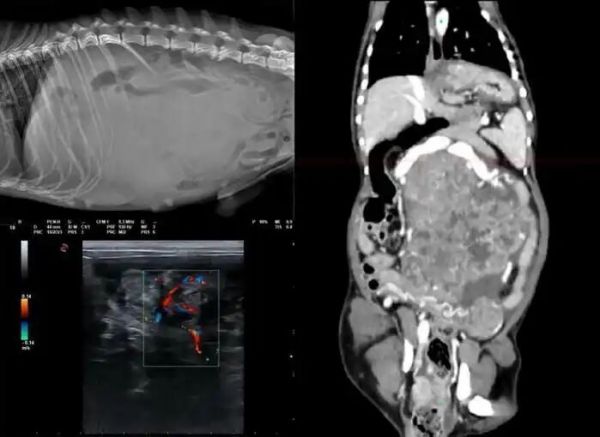

11月9日,江苏苏州一家名为ACE绿舟的宠物医院在社交平台发布了一段视频,迅速引发全网关注。视频中,一盒阳澄湖大闸蟹被整齐摆进医用CT设备,随着机器运转,屏幕上逐渐显现出每只螃蟹内部的清晰结构——蟹黄、蟹肉、蟹壳分明可见。配文称,这是出于好奇做的“小实验”。谁也没想到,这波操作让“宠物医院用CT检查蟹黄多不多”冲上热搜。

这并非恶搞,也不是营销噱头,而是一次真实发生的技术演示。医院工作人员回应称,CT本就是用来观察生物内部结构的工具,而蟹黄和蟹肉密度不同,在影像上自然能区分开来。他们只是“碰巧手边有蟹”,便想试试看。

CT(计算机断层扫描)是医院里的高端设备,通常用于诊断宠物骨折、肿瘤或脑部疾病。它通过X射线从多个角度扫描,利用计算机重建出横断面图像,能清晰显示不同组织的密度差异。正因为这种高精度成像能力,连小小的蟹黄也无法“藏身”。从技术角度看,扫描大闸蟹并无障碍,就像科研中常用微CT观察昆虫或骨骼样本一样,属于可行范围内的非典型应用。